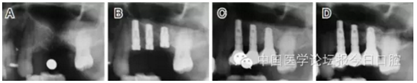

臨床上,可使用曲面體層放射線法及CT掃描方法對上額竇及可用骨量進(jìn)行評估。其中曲面體層放射線法可提供多數(shù)病例的硬腭致密影像,為治療計(jì)劃提供有價(jià)值的參考(圖1);而使用CT掃描可提供骨密度信息。如骨高度、密度、牙槽嵴的方向位置,皮質(zhì)骨和松質(zhì)骨的特點(diǎn),上頜竇黏膜厚度,病理狀態(tài)等。顯然,在上頜竇底提升術(shù)中,CT掃描影像的信息對于手術(shù)設(shè)計(jì)和減少治療風(fēng)險(xiǎn)非常重要。

圖1 采用曲面體層放射線法評估